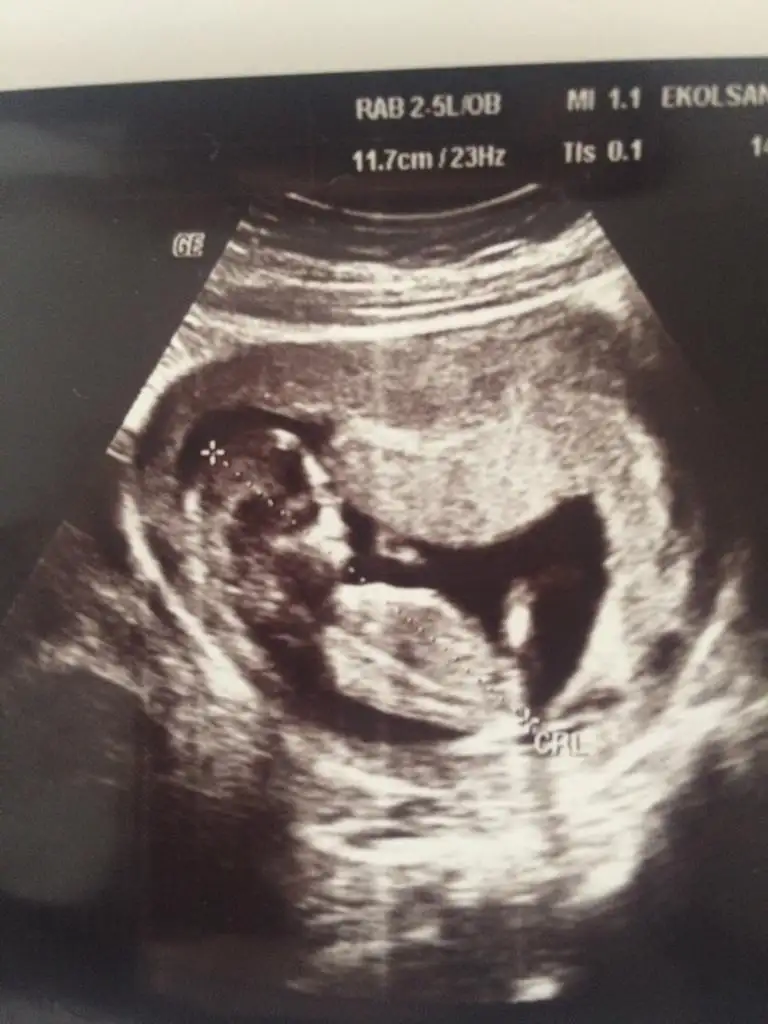

Erkek bebişarkadaşlar merhaba 12.hafta görüntüsü bebeğimin doktor erkek gibi konuştu ama net birşey demedi sizin tahmininiz nedir?Eki Görüntüle 2560931 Eki Görüntüle 2560931

teşekkürler bana da öyle geliyor bacak arası çıkıntı çok belirgin gibiErkek bebiş